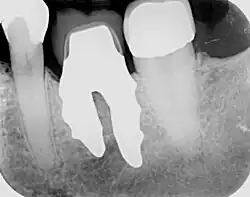

RAIs are custom made to perfectly fit the tooth socket of a specific patient immediately after tooth extraction. Therefore every implant is unique. As an optimised root-form it is much more than a simple 1:1 replica of a tooth. Since it exactly fills the gap left after the tooth is extracted, surgery is rarely needed. The implant can be produced from a copy of the extracted tooth, an impression of the tooth socket, or from a CT scan or CBCT scan.[7] The advantage of a CBCT scan is that the implant can be produced before extraction. With the former methods, it takes one or two days to fabricate an implant.

A root analogue implant can be fabricated from zirconium dioxide (zirconia) or titanium.[8] Successful titanium RAIs have been three-dimensionally printed as porous one-piece implants, using CAD software.[9] However, zirconia is the preferred material, because it is more esthetic in colour, with no grey discolouration visible through gums.[10][5]

- Obtain the 3D form of the tooth to be replaced. This is done either through careful tooth extraction and scanning of the root, taking an impression of the tooth socket, or a pre-op CBCT scan. The root analogue implant is produced using modern CAD/CAM technology, based on the principle of differentiated osseointegration;

- Placement of the root analogue implant by tapping it in. In general, no surgery is necessary. In particular, no sinus lift or invasive surgery is ever necessary. The implant is placed immediately if it has been produced beforehand from a CBCT scan, or the next day if root has to be scanned or an impression of the socket is used. A protective splint is fitted to protect the implant during the healing period.

Recovery time is very fast as neither soft nor hard tissue is traumatised. Typically, even the day after implant placement there is no swelling, bruising or pain. After 8–12 weeks' healing period, the final crown may be fitted by a family dentist.